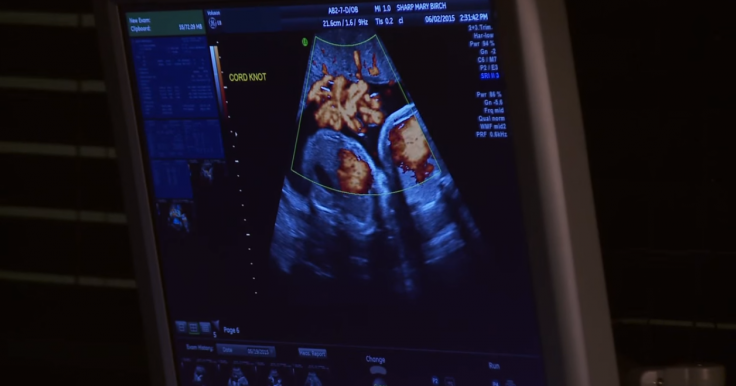

▼下图为佳思敏的超音波画面,腹中的两个胎儿共用同一个羊膜囊,这是只有2%的双胞胎宝宝才会出现的特别情况哦!

▼就在佳思敏进行产检时,医生发现小姐妹除了有脐带相互缠绕的情形之外,其中一个宝宝还处于被脐带绕颈的险境。但是若是此时就为佳思敏进行剖腹产的话,过早出世的宝宝们身体器官都发育得不够完善,同样是具有非常大的风险。

▼于是,在Sharp Mary Birch妇产医院的密切观察之下,佳思敏和宝宝们都撑过了漫长的12个星期,终于等到了适合进行剖腹产的时刻啦! 非常幸运地,两宝顺利出世了,而且这一对小姐妹都非常地健康,还可以自行呼吸,总算是化险为夷了哦!